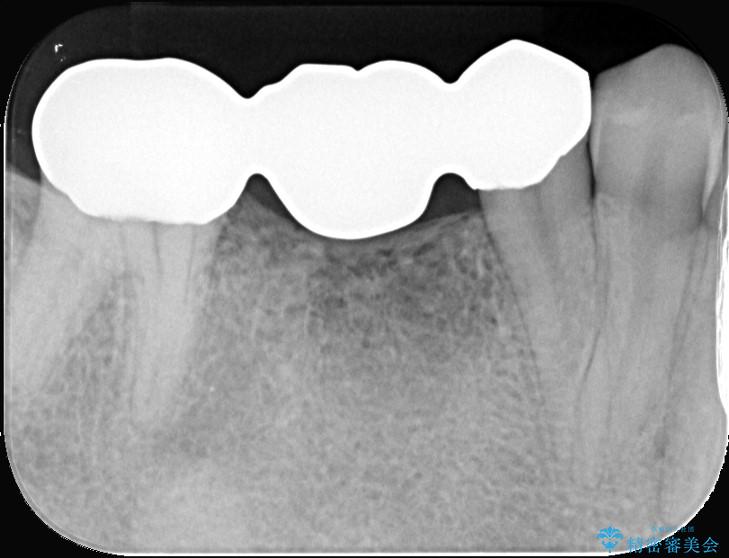

ブリッジは汚れが溜まりやすく、土台となる歯への負担も大きいため、患者様の希望に合わせそれぞれの歯をインプラント治療で独立させる治療計画を立てました。

ブリッジを外し、欠損している6番にインプラントを埋入。土台となっていた5番と7番は、セラミッククラウンで修復。

インプラント周囲の歯肉が薄かったため、FGG(遊離歯肉移植術)を行い、長期安定に不可欠な「角化歯肉」を確保しました。